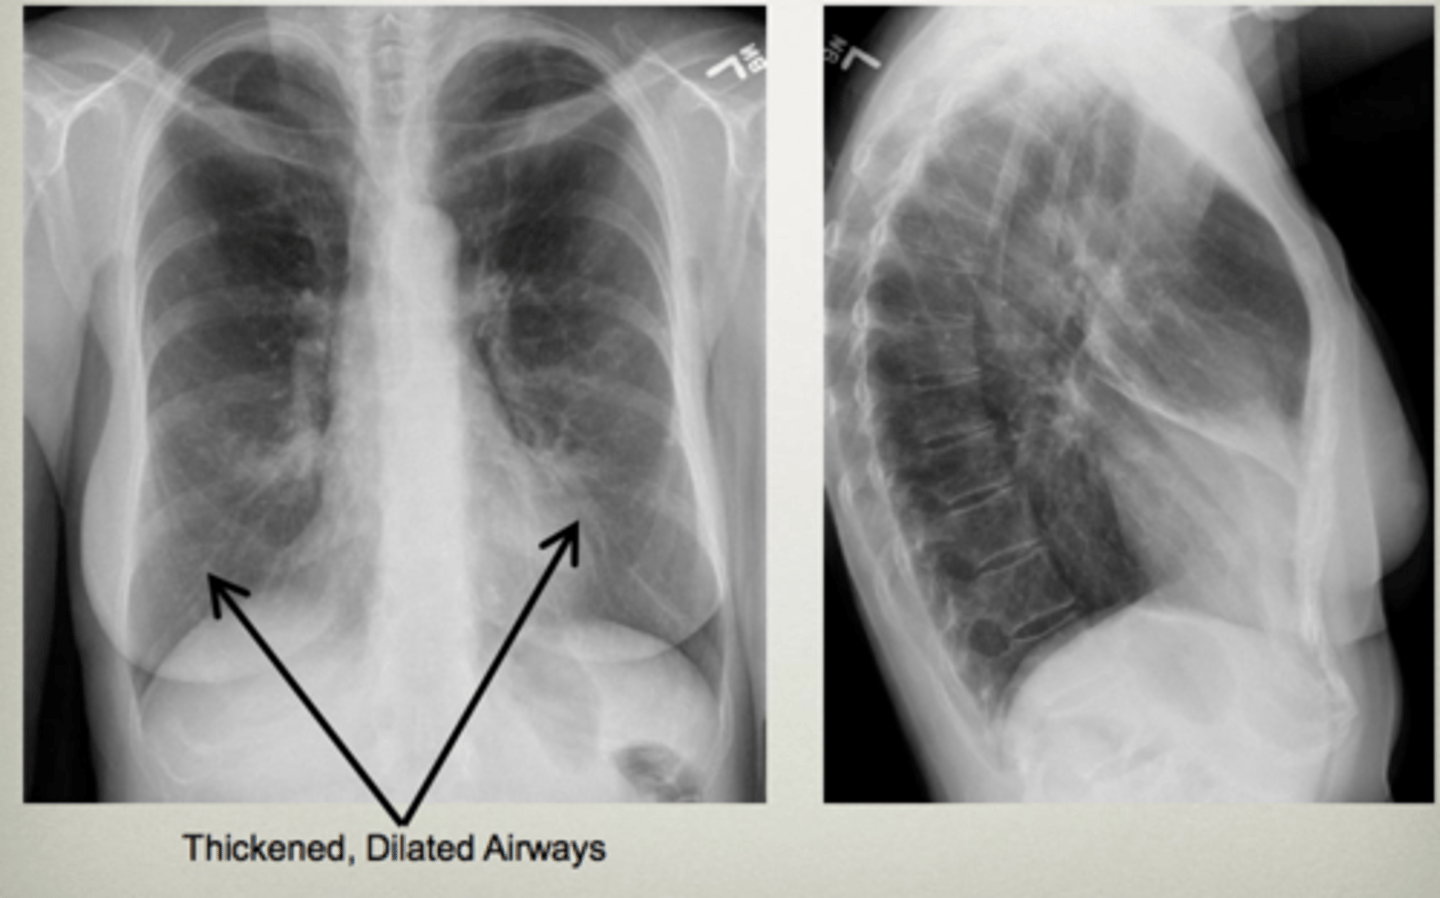

COPD/Emphysema

knowt flashcard image